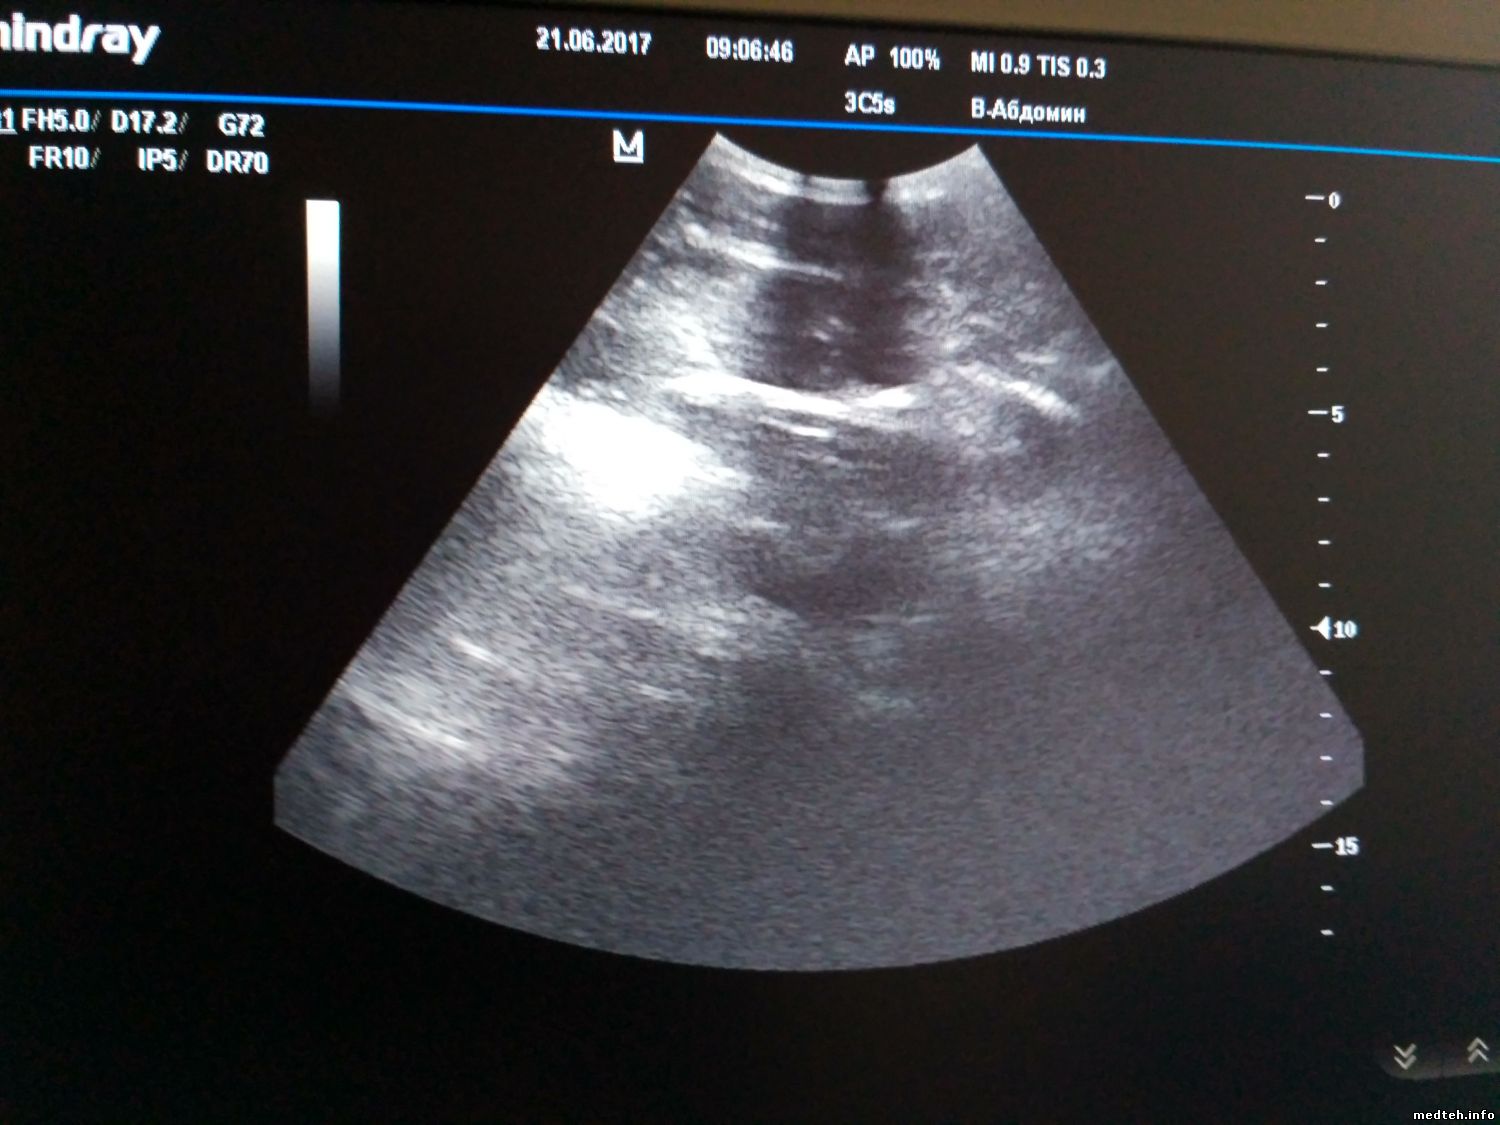

У Mindray M5 появились затемнения в виде двух полосок, которые срастаются в пятно по центру, при этом такая картина идентична на разных видах датчиков. Когда конвексный подключил к другому Миндрею М5, то там всё нормально.

Разъёмы смотрел, окиси нет, не гнутые.

Может есть калибровки или это железо глючит?

8885968.jpg (156.5 Kb)

Просто последний был конвексный. На первом фото полосы есть, на втором их нет (датчик один и тот же, аппараты разные).

1762746.jpg (148.7 Kb) · 7828479.jpg (158.8 Kb)